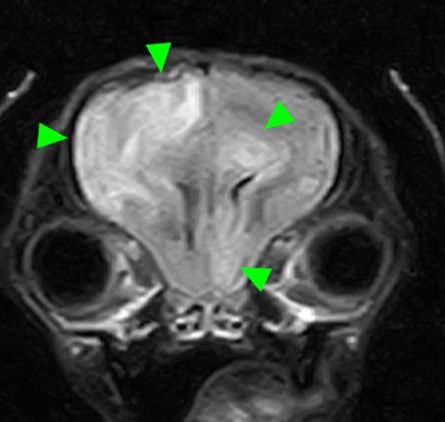

本症例のMRI検査所見:

・前頭葉白質領域(右>左)および右側大脳白質領域(側頭葉・後頭葉)にT2強調画像/FLAIR画像で高信号を示し、一部造影増強を示すびまん性の所見を認める。この所見は、DWI画像で高信号を示し、ADC-mapで大半は等~低信号を示す。

・透明中隔は欠損を疑うが、顕著な側脳室拡大を疑う所見は認められず、脳溝も明瞭である。